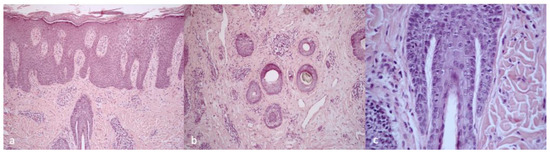

| 1 | 25/F | UCMD | COL6A1 c.850G>A | Keloids, follicular hyperkeratosis | Severe itching | White-yellow scales | Erythema, twisted red loop vessels, and yellow interfollicular scales | Dilated vessels in the dermis; parakeratosis, focal absence of granular layer in the epidermis, and neutrophilic infiltrate in the papillary dermis mantles (sebaceous structures) |

| 2 | 29/F | UCMD | COL6A1 c.958-2A>G | Face and neck hirsutism, keloids | Severe itching | Small cicatricial areas on vertex | Tufted hair, absence of follicular ostia in cicatricial area, and dilated elongated vessels | Dense diffuse suppurative, mixed infiltrate in the dermis. “Tufted folliculitis” and intraepidermal pustules |

| 3 | 24/F | UCMD | COL6A2 homozygous c.348dup | Keloids | Mild itching | Cicatricial patch on vertex | Severe erythema, dilated vessels, yellow scales, tufted hair, perifollicular pustules, and cicatricial areas with absence of follicular ostia | Superficial perivascular and perifollicular infiltrates of lymphocytes and neutrophils |

| 4 | 37/F | UCMD | COL6A2 c.875G>T | Keloids, follicular hyperkeratosis | Severe itching | Fine scaling | Perifollicular scales and erythema | Superficial perivascular and perifollicular infiltrates of lymphocytes and neutrophils; collection of neutrophils within infundibula |

| 5 | 24/M | UCMD | COL6A1 c.930+189C>T | Keloids, follicular hyperkeratosis | Severe itching | Hair thinning | Different hair diameters, erythema, dilated vessels, and yellow scales | Superficial perivascular and perifollicular infiltrates of lymphocytes and neutrophils |